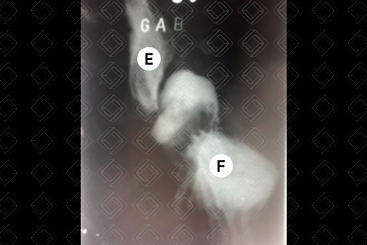

Texto alternativo para a imagem Figura 2. Créditos: Dra. Elazir Mota - Rio de Janeiro/RJ

Texto alternativo para a imagem Figura 3. Créditos: Dra. Elazir Mota - Rio de Janeiro/RJ

Descrição das figuras 2 e 3: Estudo contrastado (trânsito de delgado) evidenciando hérnia hiatal por deslizamento. Observar que neste tipo de hérnia, a junção esofagogástrica encontra-se em posição mais alta do que a habitual (seta vermelha).